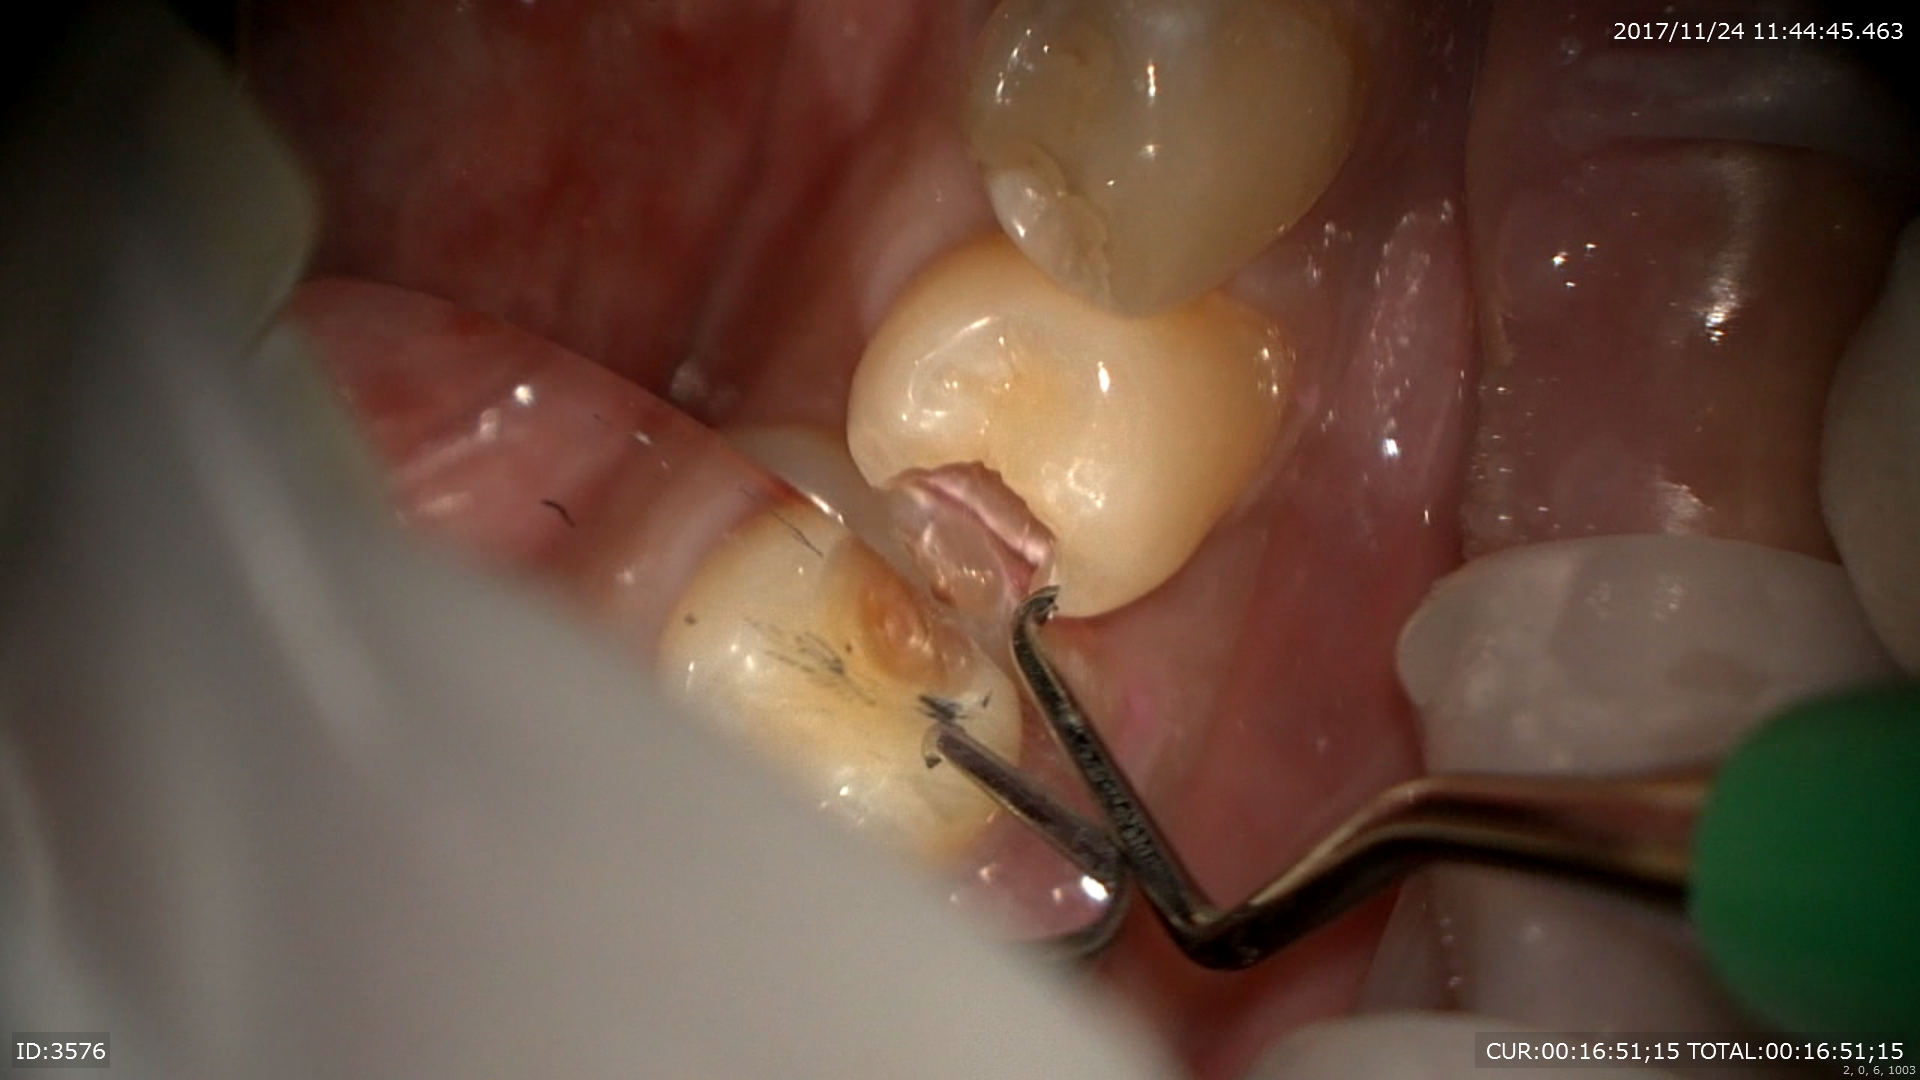

マイクロエンド

今日は2回目

右が前回左は本日

綺麗になりました。

2回目で治療が終わりました。根管充填。